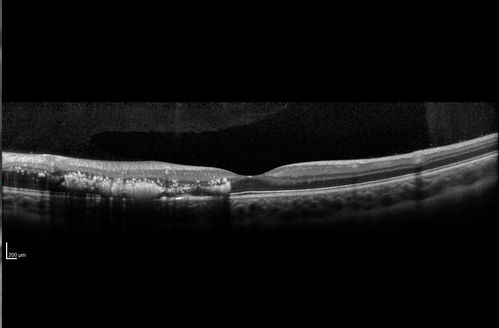

Coats' Disease - 14 year old - Asymptomatic

Presented with macular exudates. Temporal macroaneurysms responded to laser. Ultra-wide field FA shows nonperfusion

Coats' Disease - 14 year old - Macular Exudates